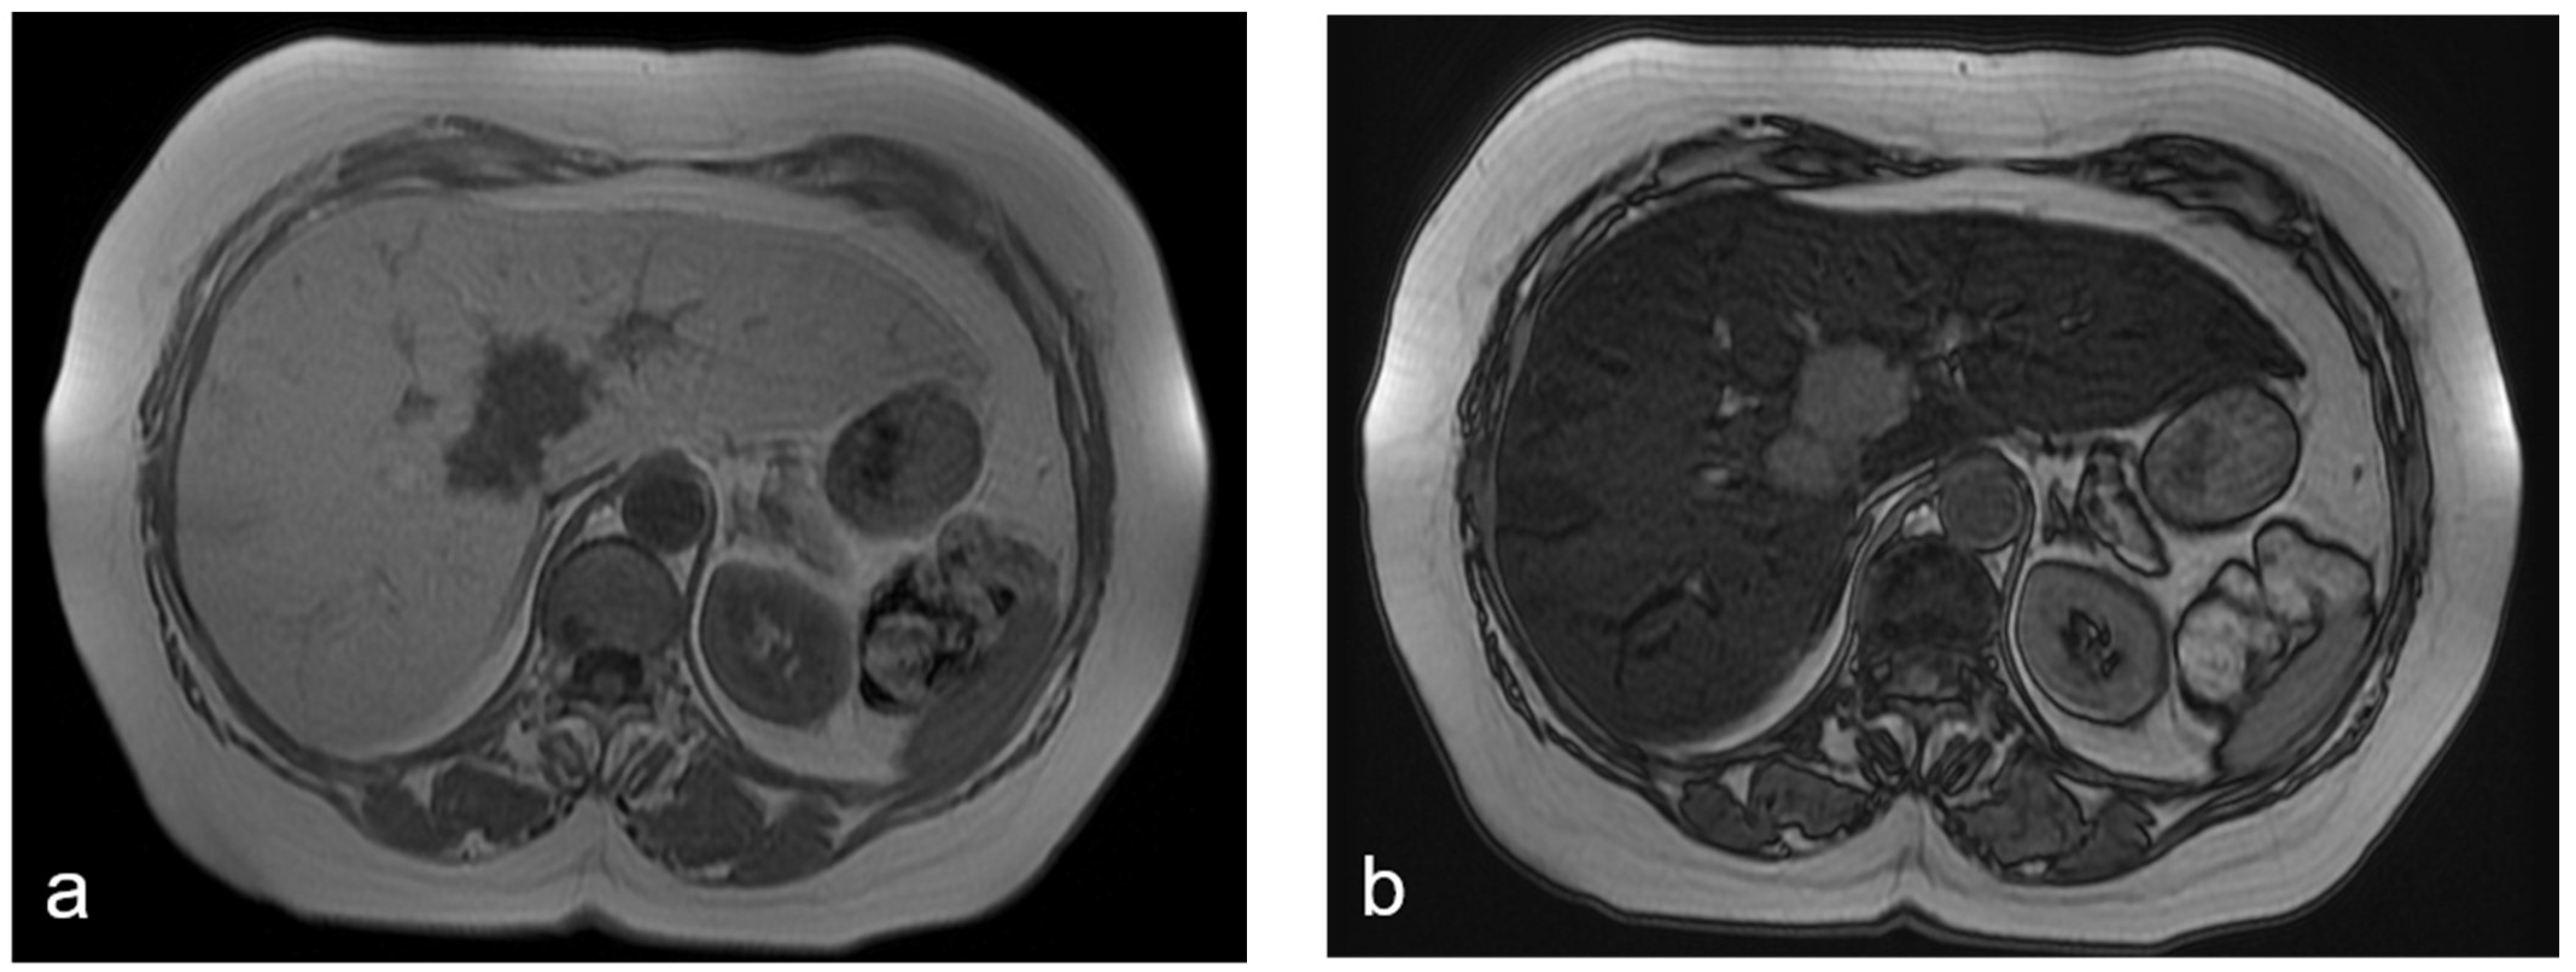

NRH appears hypointense in the T1-weighted images and hyperintense in the T2-weighted images; the gadoxetic acid-enhanced MRI shows the lesions as slightly enhanced areas in the vascular phase and as hypointense areas in the HB phase; and the absence of diffusion restrictions in DW-MRI excludes the possibility of liver metastases [6,44,45,46] (Figure 6).

Figure 6.

(a–d) A 52-year-old woman with hepatic metastases from colon cancer undergoing neo-adjuvant chemotherapy with folinic acid, 5-fluorouracil, oxaliplatin, and irinotecan (FOLFOXIRI). After chemotherapy, a new centimetric lesion appeared in segment 7 (arrow). The lesion was not appreciable in the T2-weighted image (a) or in the DW-MRI image, with b-values of 1000 s/mm2 (b). After the administration of Gd-EOB-DTPA, the lesion appeared hyperintense in the arterial phase image (c) and slightly hypointense in the hepatobiliary phase image (d) and was not easily recognizable from the surrounding hepatic parenchyma, which is markedly inhomogeneous and suggestive of SOS. The findings are consistent with an NHR lesion.